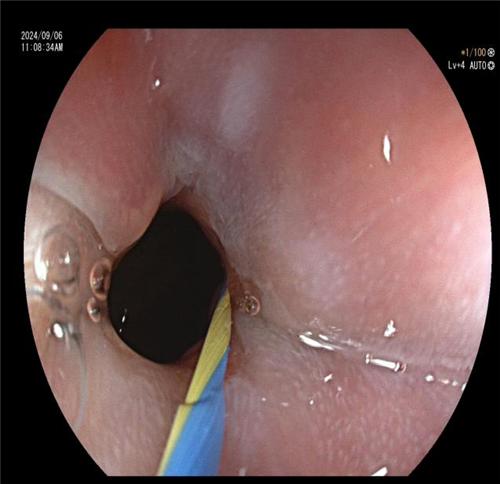

食管钡剂造影显示不同程度的食管扩张(钡剂潴留)以及食管下端变窄呈「鸟嘴样」改变,这是贲门失弛缓症的重要诊断依据。曾主任与患者及家属充分沟通后,决定为其施行 “内镜下贲门大球囊扩张” 治疗。该治疗的基本原理是将气囊置入食管内,再向气囊内注入气体,使其扩张到一定程度,使 LES 的肌纤维断裂,从而达到松弛 LES 的效果。术后,患者恢复良好。